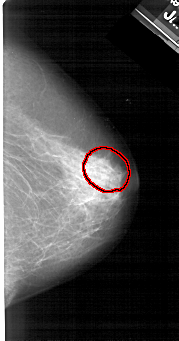

A_1378_1.LEFT_CC

FILE: A_1378_1.LEFT_CC.OVERLAY

TOTAL_ABNORMALITIES 1

ABNORMALITY 1

LESION_TYPE CALCIFICATION TYPE PLEOMORPHIC DISTRIBUTION CLUSTERED

ASSESSMENT 4

SUBTLETY 4

PATHOLOGY BENIGN

TOTAL_OUTLINES 1

BOUNDARY